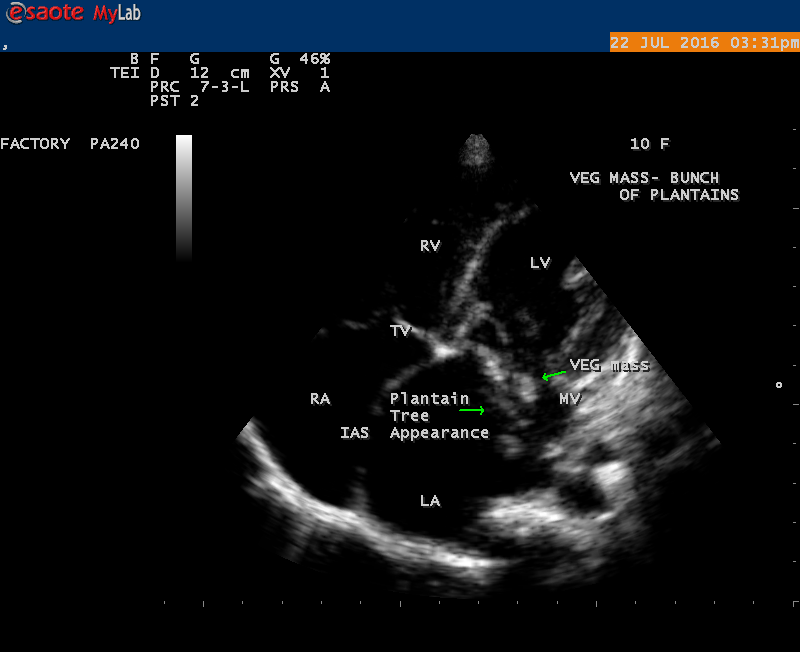

The most common and direct evidence of infective endocarditis is the vegetation and it begins as a microscopic focus of infection and gradually grows into a conspicuous mass. It is typically an irregularly shaped, highly mobile, echogenic mass attached to the free edge of a valve leaflet ( most commonly at the coaptation line) and tends to develop on the ‘upstream’ side of the valve leaflets ( ie, the ventricular side of aortic valve and the atrial side of mitral and tricuspid valves. They may be seesile or pedunculated, but usually has an oscillating or fluttering motion, a typical feature of most vegetations. Vegetation move with the leaflet in a more chaotic (‘oscillating’) manner and it may prolapse through the valve into the LV (left ventricle) as it opens as shown in Figures 3, 4 and 16 and into LA (left atrium) as it closing (Figure 5 and 6) . The mass of vegetation is typically homogeneous with echogenicity similar to that of the myocardium. The infectious process often alter the valvular structure and function. Extensive involvement of the leaflet may result in chordal rupture, leading to severe regurgitation as shown in Figure 21 . Direct and typical signs of RMCT (ruptured mitral chordate tendineae) were chain-flail or whiplash-like changes and had an incidence of 86.7%, causing severe regurgitation and mitral chordal rupture is the leading cause of flail mitral leaflet[30]. A large vegetation may obstruct the valve orifice as shown in Figure 1 and 2 , sometimes termed as “obstructive-type bacterial endocarditis” and producing a functional valve stenosis ( Ping-Pong mitral stenosis [31]) similar to left atrial myxoma as shown in Figure 29.

The shape of vegetation varies in this child as ‘popcorn’ like (Figures 1,3 and 4 ), rod-shaped (Figure ), basket shaped (Figure 7 )[33-Figure 13.3], ‘baby in hand’ appearance (Figure 18), ‘cucumber shaped (Figure 2 ) and a ‘bunch of plantain’appearance (Figure 33 ), ring shaped (Figure 19 }, bileaflet structure (Figure 9 )with bileaflet MR jet as shown in Figure 10 . and kissing forms (Figure 13 - parasternal long axis view, Figure 14 - apical four chamber view and Figure 15 - short axis view)